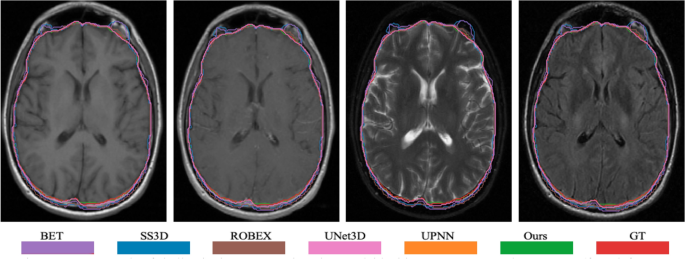

In the work, we also compare the performance of skull stripping using the proposed deep learning-based method to the popular methods/tools. The selectively popular tools include three traditional computer vision-based methods and two deep learning-based methods. In doing so, we either re-implement the algorithm or directly use the published tools. The popular methods/tools include Brain Extraction Tool (BET)23, 3d skull stripping (3dSS)47, Robust Learning-Based Brain Extraction (ROBEX)48, UNet 3D (UNet3D)38, and DeepMedic by UPNN39. The main difference between the two deep learning-based methods and the proposed method is the feature ensemble part in the network. We argue that the adding more context features leads to a better skull stripping. We apply the exactly same pre-processing steps as described in Fig. 1 to all methods for the state-of-the-art comparison. For the UNet3D method, we re-implement the architecture and re-train CNN network using our dataset, which has exactly same data distribution as to the proposed method. However, for the DeepMedic method, we directly apply the pre-trained model to our data. An example case showing contours overlaid with the multiparametric sequence is shown in Fig. 3. The visualization skull stripping comparison is shown in Fig. 4 and the quantitative performance comparison is listed in Table 5. In addition, we also perform the analysis of variance (ANOVA) on dice score coefficient by comparing performances of these existing methods to our result, and the p-values are shown in the Table 5. All p-values are less than 0.001, which implies the proposed method providing a significant improvement on the skull stripping. The boxplot comparison of state-of-the-art is shown in Fig. 5.

The performance comparison demonstrates that the proposed method offers the best results in terms of the dice, precision, recall, FPR, FNR, and the HD95. The small value of the standard deviation indicates the robustness of the skull stripping performance. We also notice an interesting thing: the BET has better performances on Recall and FPN, comparing to the proposed method. It may be that BET using T1 and T2 image modalities generates less false negatives. However, it produces lots of false positives.